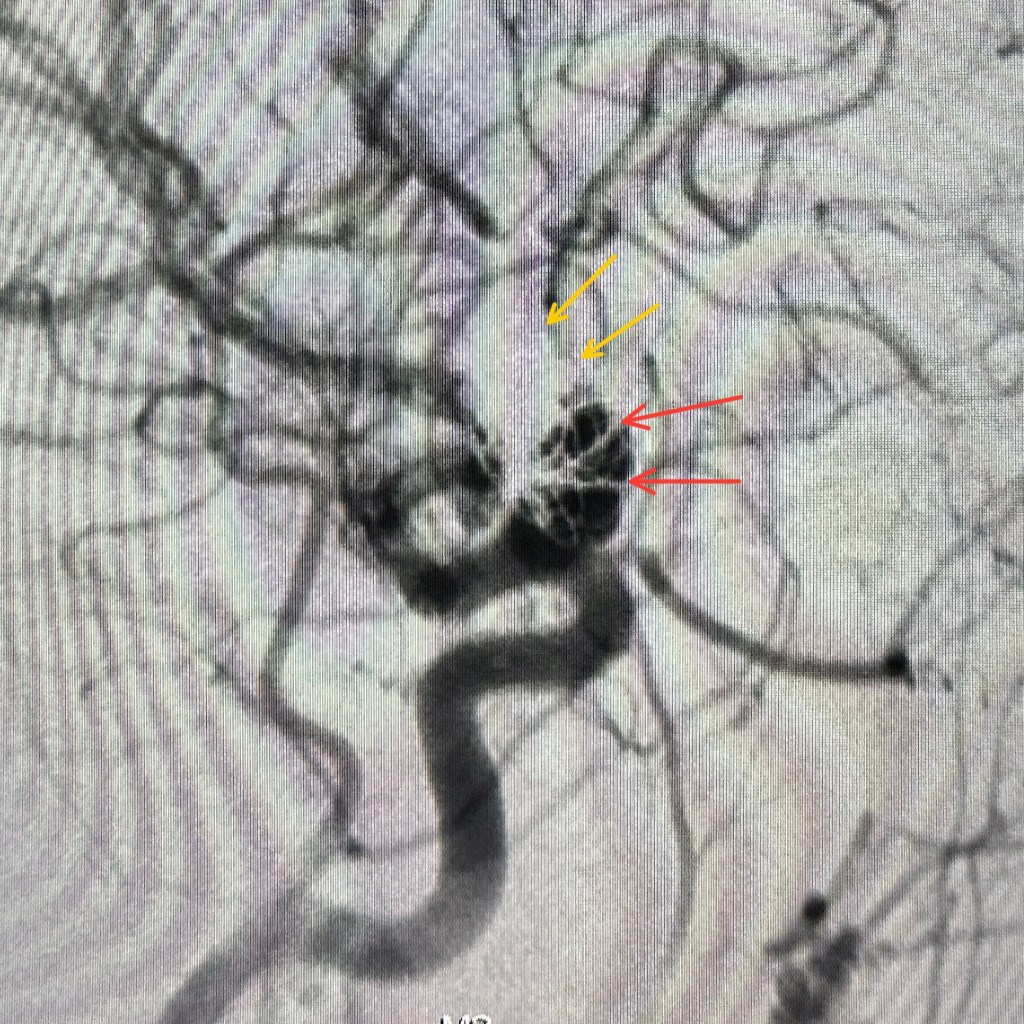

في الصورة الأولى:

السهم الأصفر 🟡 بيشاور على الملفات الحلزونية القديمة.

والأسهم الحمراء 🔴 بتوضح الجزء اللي حصل فيه نمو جديد.